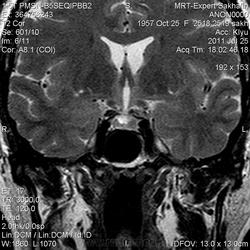

Как мы "динамичим"гипофиз

Женщина.6 лет назад выявлено образование левой доли нейрогипофиза.Пришла на контроль.

Постконтраст

Мне самой показался случай не совсем ясным, но динамик четко показывает участок с отставанием в контрастировании, воронка смещена вправо-о чем  думать бедному начинающему специалисту?

Кстати, немного о внимательности-номера протоколов могут многое подсказать!